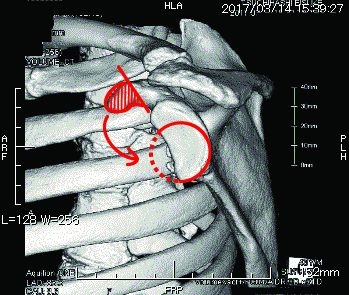

ラグビーや柔道で受傷した慢性的な肩関節前方不安定症 肩関節脱臼 骨欠損を伴った症例 その2 Latarjet法 ラタジェット法 がっちり治して炎のタックル スポーツ整形外科医s Uのブログ Sports Physician S U Blog